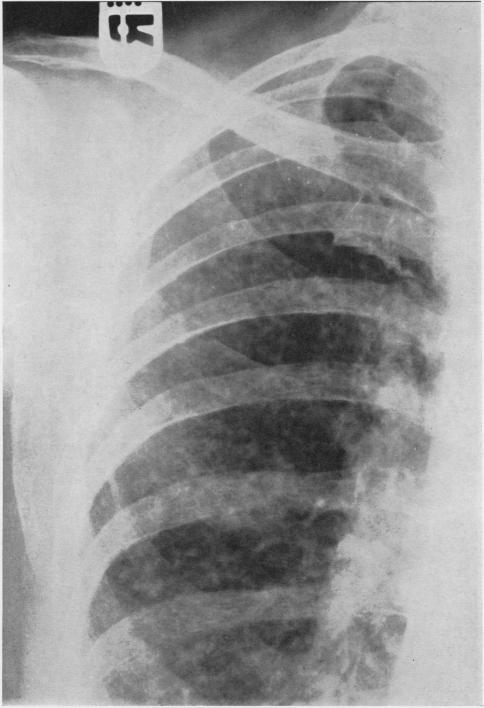

Rheumatoid arthritis with lung lesions.

Thorax. 1956 Sep;11(3):234-40. doi: 10.1136/thx.11.3.234.